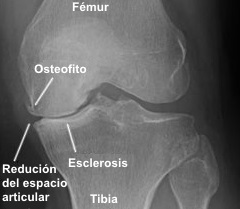

Radiografía de artrosis

🩻 Signos radiológicos

Los signos radiológicos cardinales son:

• Disminución de la interlínea articular: refleja la pérdida del cartílago.

• Osteofitos: proliferaciones óseas en los márgenes articulares, resultado de la reacción del hueso subcondral ante la destrucción cartilaginosa. Están recubiertos de fibrocartílago.

• Esclerosis del hueso subcondral: aumento de la densidad ósea bajo el cartílago.

• Geodas o quistes subcondrales: visibles en ciertas localizaciones como la cadera, por hiperpresión intraarticular que escapa a través de fallas en la cortical.

Como signo negativo, no se observa osteoporosis regional.

En estadios tempranos, la radiografía puede ser normal. En casos avanzados, son comunes grandes deformidades y subluxaciones. Es importante destacar que en sujetos asintomáticos pueden aparecer signos radiológicos (como osteofitos) y que más del 40 % de los que presentan signos radiológicos de artrosis no tienen clínica.